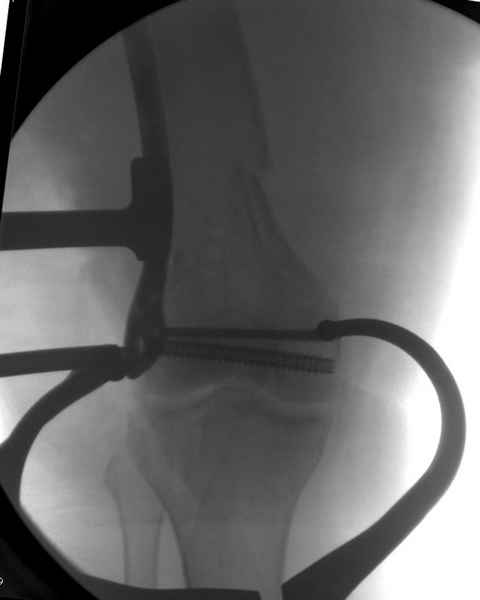

Уважаемые коллеги! От имени Алексея Смирнова всем спасибо за обсуждение. Больной прооперирован. Снимки в приложении.